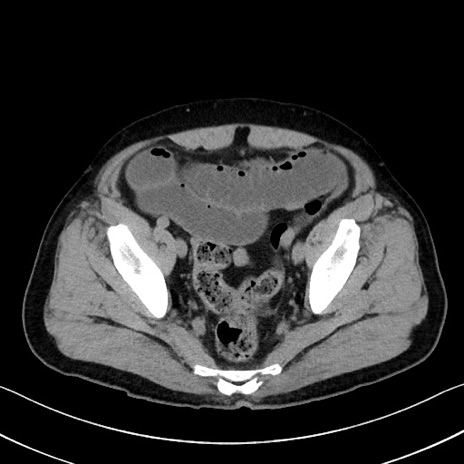

冠状断像

症例35(横断像)

【症例】70歳代 男性

【主訴】腹部膨満、嘔吐

【現病歴】昨日より腹部膨満感出現。本日増悪し、仙痛出現。嘔吐あり、受診。

【既往歴】糖尿病、胆摘後

【身体所見】BP 149/80mmHg、HR 74/min、BT 35.9℃、腹部:膨満、軟、圧痛なし。腸雑音減弱あり。上腹部正中切開瘢痕あり。

【データ】WBC 13500、CRP 1.72